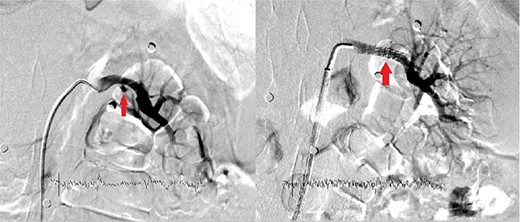

The patient was re-evaluated with CTA 3 weeks after discharge. Endovascular intervention was planned after observing that the left RAP was enlarged to 6 mm (Fig. 2). A renal angiogram was performed. After selectively catheterizing the left renal artery, a 6 × 3 mm filling extending inferiorly in the middle part of the left renal artery compatible with RAP was observed (Fig. 3). Following catheterization of the left renal artery with a long sheath, the lesion segment was passed with guide wire-catheter manipulations. Subsequently, a 6 × 22 mm covered stent (Advanta V12 Balloon Expandable Covered Stent, AMC, USA) was placed to include the RAP neck, and full expansion of the balloon and stent was achieved (Fig. 3). The control images revealed that the RAP was excluded from circulation, and the stent was patent. No embolism or bleeding was observed in the distal renal artery branches.

The filling image of the left renal pseudoaneurysm and the inserted covered stent.